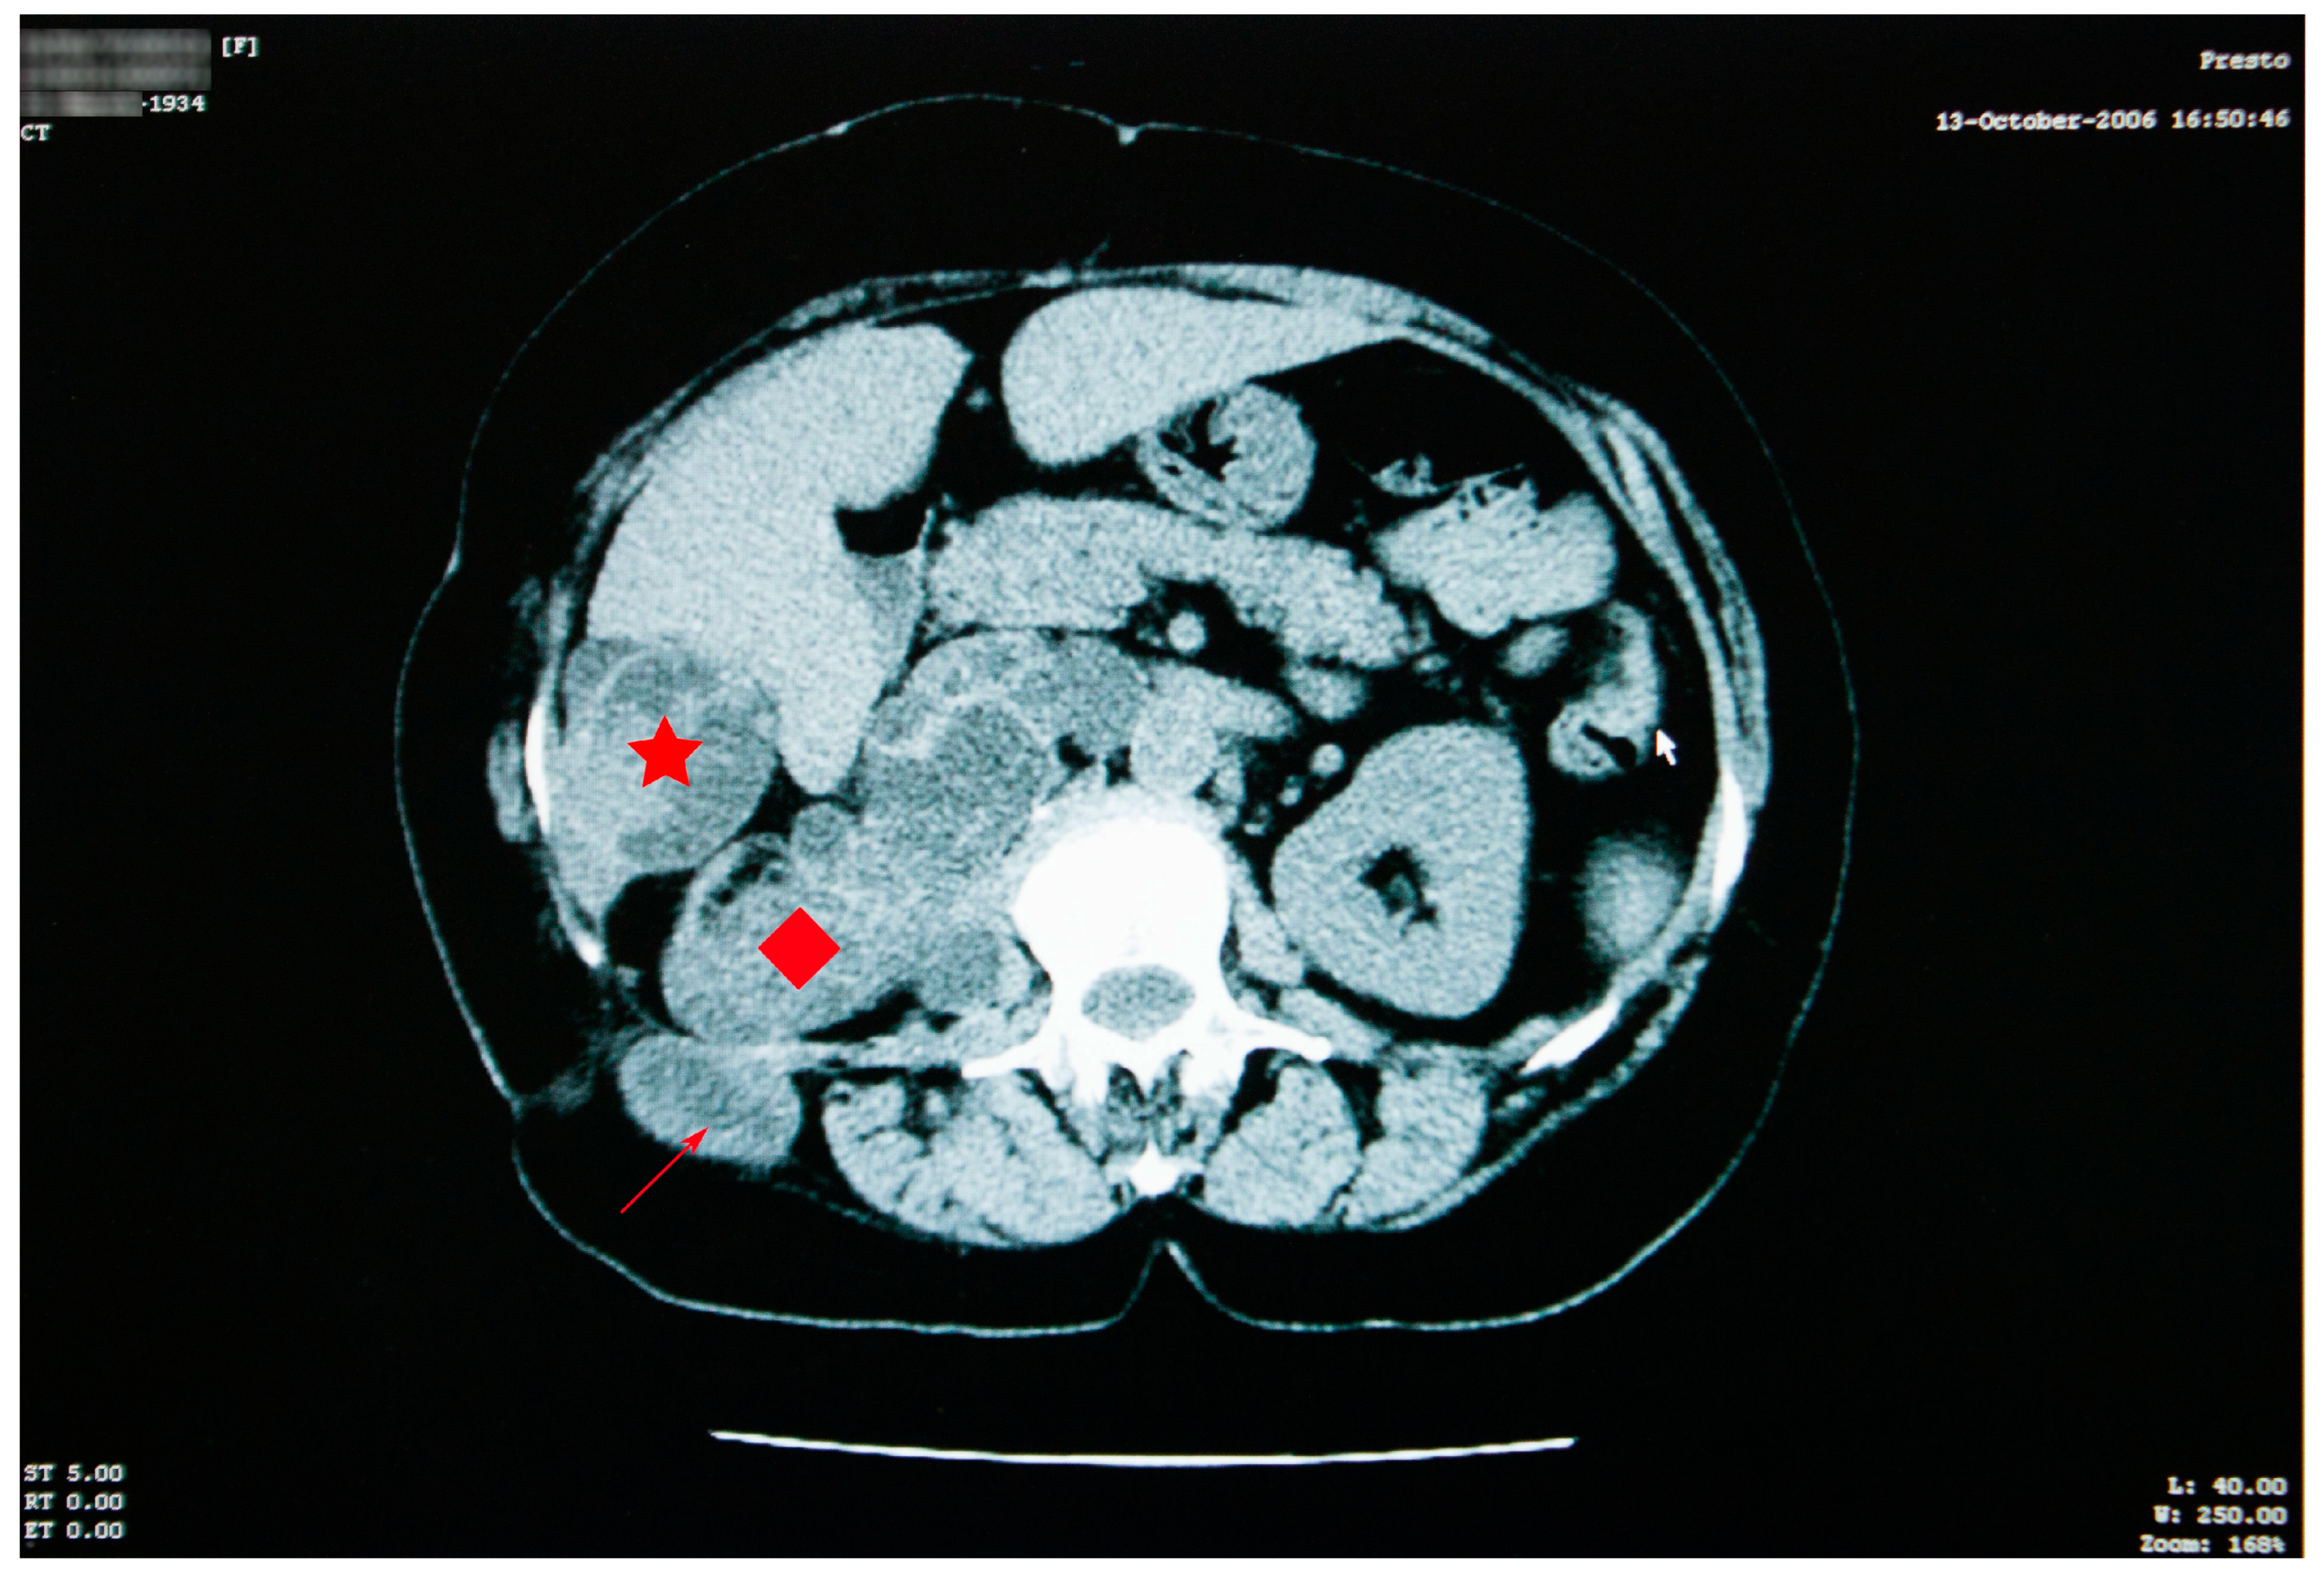

The abdominal CT scan showed multiple spontaneous hypodense masses with hyperdense borders, occupying the entire kidney space, with no evidence for the right kidney (Figure 6).

The maximum axial dimension of the above-mentioned lesions was 10 cm, which is considerably less than what was recorded in 2006. In addition, this conglomerate of hypodense images was remarked to have increased in overall density. The conglomerate presented cranial and caudal extension, starting just beneath the diaphragm and ending right under the plane of the renal artery, with a close anatomic relation to the right diaphragm pillar, right hemidiaphragm, and right psoas muscle. The spontaneous hypodense, heterogenous mass, with an axial maximum diameter of 46 mm, located in the VI liver segment, appeared to be reduced in comparison to the 2006 examination.

Figure 6. Abdominal CT shows reduction in the aspect and dimensions of the cysts—right kidney space (red diamond), the sixth right liver segment (star) and in the right iliac fossa and right paravertebral area (arrow)—associated with favorable evolution under treatment.